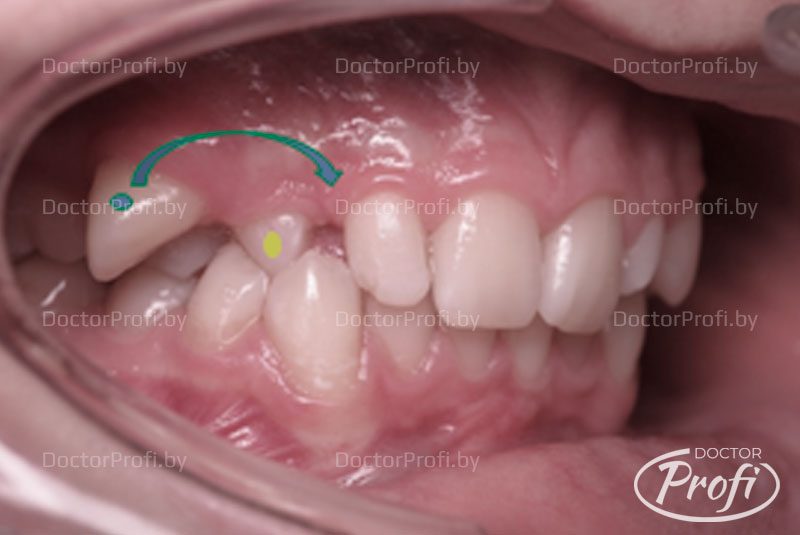

Транспозиция зубов – это сложная аномалия положения зубов, когда два зуба меняются местами друг с другом.

Пациентка обратилась в клинику с жалобами на серьезные проблемы с положением зубов, связанные с транспозицией верхнего правого клыка с премоляром и микродентией боковых резцов.

В результате проведенного лечения мы получили возвращение зубов (клыка 1.3 и премоляра 1.4) на свои места и хорошее функциональное и эстетическое состояние. Лечение брекет-системой помогло обрести красивую улыбку и симметрию лица.